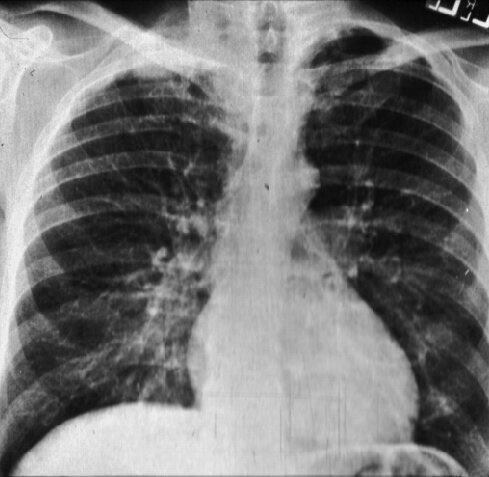

حالة طوارئ مخيفه ! عنده Psoarisis و COPD قبل اسبوع جاء الطوارئ ب COPD exacerbation وعطوه العلاج الاساسي اللي يتضمن steroids الان رجع بطفح في كل جسمه ..... التشخيص ؟